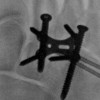

Indications for operative versus nonoperative treatment of tarsometatarsal joint injuries depend on the specific injury pattern and disruption of normal anatomy, which may be evident on physical examination or radiographs but may also present more subtly.

By Andrew Rosenbaum, MD, John DiPreta, MD, and Richard Uhl, MD